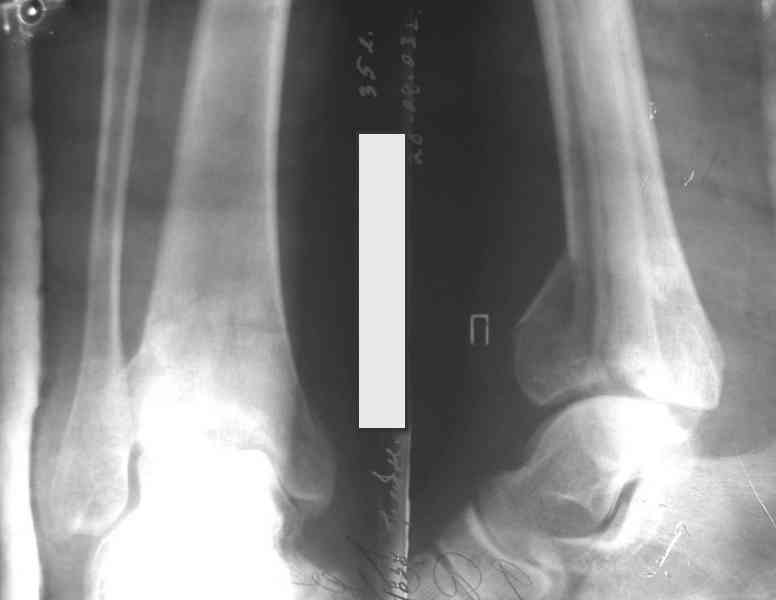

Re: Perelom N/3 kostei goleny

Дрягин В. 04 Январь 2007, 09:01

Послала ещё два снимка, если не пройдут, пошлю ещё. Дрягин. Если есть вопросы, готов ответить.